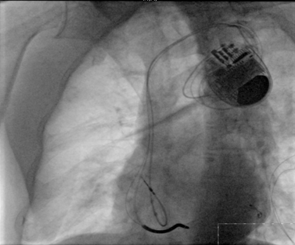

? CRT-D成功植入

?“它的技術(shù)難點(diǎn)在于左室電極的植入”。朱彬介紹,除了常規(guī)的由于心臟擴(kuò)大變形所致的冠狀靜脈竇口位置改變,自身冠狀靜脈解剖異常等問題外,傳統(tǒng)的左室電極安置后存在起搏位點(diǎn)選擇性小,起搏時(shí)容易出現(xiàn)膈神經(jīng)或膈肌刺激、起搏高閾值、為保證穩(wěn)定性將電極植入心尖而出現(xiàn)心尖部起搏,為避免心尖部起搏避開心尖位置但卻出現(xiàn)電極不穩(wěn)定術(shù)后移位等諸多問題。而左室四極電極導(dǎo)線由于可以有多個(gè)起搏位點(diǎn)和多種起搏向量的選擇,可一次性解決上述難題,能做到“電極植入心尖,起搏心底”。綜合患者具體情況,為提高手術(shù)成功率,降低手術(shù)風(fēng)險(xiǎn),朱彬決定在該手術(shù)中使用目前國內(nèi)最新型的左室四極電極。